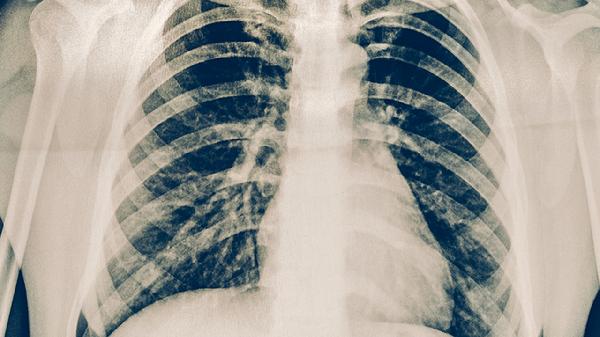

肺结核停药后出现胸疼胸闷可能与结核病灶未完全吸收、胸膜粘连、药物副作用、合并其他感染或心理因素有关。建议及时复查胸部影像学及炎症指标,排除活动性结核复发。

肺结核治疗周期通常需6-9个月,部分患者停药时肺部病灶可能仍有少量残留炎症。这些病灶可刺激胸膜或支气管,表现为间歇性胸痛伴轻微胸闷,尤其在深呼吸时加重。需通过胸部CT评估病灶纤维化程度,若存在活动性炎症需考虑延长抗结核疗程。